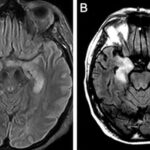

A Rare Case of Autoimmune Encephalitis: Diagnosis and Management August 25, 2024 No Comments Autoimmune encephalitis (AE) is a complex and often challenging condition to diagnose and manage. It involves inflammation of the brain caused by